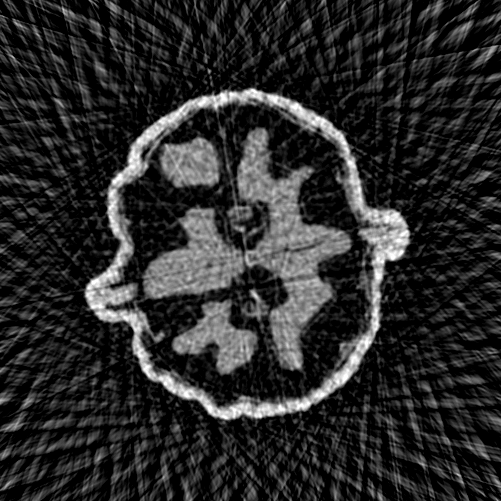

Refer to caption

(a) Eigenfunctions of the kernel 𝐉𝐉T{\mathbf{J}}{\mathbf{J}}^{T} with random input 𝐳{\mathbf{z}}

(b) Eigenfunctions of the kernel 𝐉𝐉T{\mathbf{J}}{\mathbf{J}}^{T} with FBP input

Figure 3: The first four images in each row correspond to the first 4 eigenfunctions of 𝐉𝐉T{\mathbf{J}}{\mathbf{J}}^{T}. The last image is the initial output of the (untrained) DIP. In (a) the input to the DIP is random noise, in (b) it is the FBP reconstruction of the μ\muCT walnut image.

where 𝐠(k)=𝐀T(𝐀f~𝜽(k)(𝐳)𝐲δ)\mathbf{g}^{(k)}={\mathbf{A}}^{T}({\mathbf{A}}\tilde{f}_{{\boldsymbol{\theta}}^{(k)}}({\mathbf{z}})-{\mathbf{y}}^{\delta}) is the update direction and 𝐮i{\mathbf{u}}_{i} the eigenvector for the eigenvalue σi\sigma_{i}. The update in (18) gives rise to the spectral bias of the NTK, meaning that components corresponding to larger eigenvalues σi\sigma_{i} are updated more quickly. Thus, the DIP prioritises fitting components of the solution aligning with the top eigenspaces. The spectral properties of the Jacobian 𝐉{\mathbf{J}} are both data and model-dependent, as the Jacobian is influenced by both the underlying network architecture and the input 𝐳{\mathbf{z}}. To highlight this influence, we show the top four eigenfunctions of a randomly initialised DIP in Figure 3. We compare the eigenvectors with either a random input 𝐳{\mathbf{z}} or the FBP 𝐳=𝐀𝐲δ{\mathbf{z}}={\mathbf{A}}^{\dagger}{\mathbf{y}}^{\delta} as the initial input to the network, for the same μ\muCT walnut data used in Figure 2. We see that the eigenvectors for the FBP input more closely resemble the ground truth image.